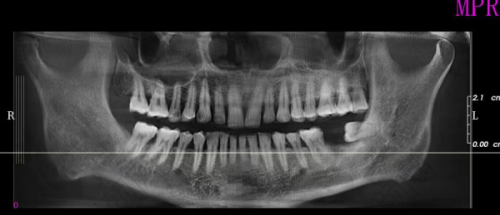

上海鼎植刘正欢种植牙实例

曾有一位患者,由于长期牙齿缺失,导致牙槽骨重度萎缩,普通的种植牙技术难以实施。刘正欢院长经过详细的检查和分析,决定为患者采用穿颧种植技术。在手术过程中,刘院长凭借不错的技艺和丰富的经验,精细操作,成功为患者植入种植体。术后,患者修复良好,牙齿功能和美观度都得到了极大的改善,对刘院长的医术赞不绝口。